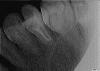

костерико Опубликовано 18 марта, 2010 Автор Поделиться Опубликовано 18 марта, 2010 (изменено) Сходила взяла снимки в эл.виде.Будьте добры посмотрите каналы,как сделаны.И все-таки я не понимаю,не развод ли это был.Где там два канала?И зубы,которые справа и слева от анкерного-их состояние.Если конечно качество подходит.Добавлю 4 снимка,какой лучше не знаю. Изменено 18 марта, 2010 пользователем костерико Ссылка на комментарий

костерико Опубликовано 18 марта, 2010 Автор Поделиться Опубликовано 18 марта, 2010 (изменено) Этот зуб и должен болеть - из двух каналов один недопломбирован,второй незапломбирован вообще.Нужен хороший эндодонтист (не за 2,5 тыщи), потом культевая вкладка и коронка. PS. И пломбу на шестом переделать. Нависающий край.это что то новое........это уже вторая переделка и что опять не переделали хорошо?а все так думают?я сейчас в обморок упаду.вообще зуб уже не болит,хотя,при постукивании по нему,он неприятно чувствителен(((А ТРЕТИЙ РАЗ МОИ КАНАЛЫ ОСИЛЯТ? Изменено 18 марта, 2010 пользователем костерико Ссылка на комментарий

zybnaya feya Опубликовано 18 марта, 2010 Поделиться Опубликовано 18 марта, 2010 это что то новое........это уже вторая переделка и что опять не переделали хорошо?а все так думают?я сейчас в обморок упаду.вообще зуб уже не болит,хотя,при постукивании по нему,он неприятно чувствителен(((А ТРЕТИЙ РАЗ МОИ КАНАЛЫ ОСИЛЯТ? Костерико,вы хоть бы пронумеровали сним. Где ДО ,а где ПОСЛЕ?? Если тот что самый последний,так он мутный и не информативен. Все остальные я так поняла сделаны ДО последнего (второго)вмешательства? Ссылка на комментарий

костерико Опубликовано 18 марта, 2010 Автор Поделиться Опубликовано 18 марта, 2010 (изменено) Костерико,вы хоть бы пронумеровали сним. Где ДО ,а где ПОСЛЕ?? Если тот что самый последний,так он мутный и не информативен. Все остальные я так поняла сделаны ДО последнего (второго)вмешательства?нет,все СНИМКИ СДЕЛАНЫ ПОСЛЕ ПЛОМБИРОВКИ каналов.НА НИХ ГОТОВЫЙ РЕЗУЛЬТАТ.доктор все сделан, потом рентген,сказал все супер. Изменено 18 марта, 2010 пользователем костерико Ссылка на комментарий

zybnaya feya Опубликовано 18 марта, 2010 Поделиться Опубликовано 18 марта, 2010 нет,все СНИМКИ СДЕЛАНЫ ПОСЛЕ ПЛОМБИРОВКИ каналов.НА НИХ ГОТОВЫЙ РЕЗУЛЬТАТ.доктор все сделан, потом рентген,сказал все супер.Если ЭТО окончательная пломбировка,то +10000 к мнению Fury Канал не пролечен до апекса(а их 2) и весь просвет в порах,что свидетельствует о его вустотк в просвете. Очень жаль это говорить-но перелечивать его надо снова Ссылка на комментарий